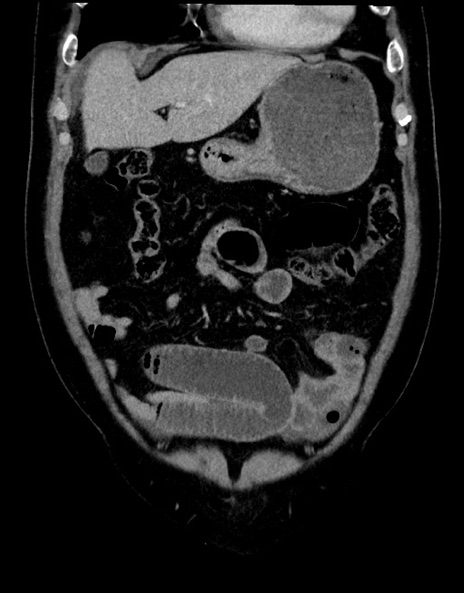

症例15(冠状断像)

【症例】70歳代男性

【主訴】腹痛

【現病歴】今朝から腹痛あり。全体的に痛い。特に左上の方。排ガスが今日はない。冷や汗が出る。

【既往歴】直腸癌術後

【身体所見】左側腹部〜上腹部に圧痛あり。腹膜刺激症状明らかなではない。軽度反跳痛。左下腹部に術後瘢痕あり。

【データ】WBC 7700、CRP 0.02